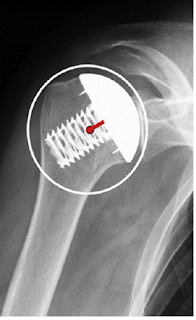

The authors of Screw fixation in stemless shoulder arthroplasty for the treatment of primary osteoarthritis leads to less osteolysis when compared to impaction fixation compared their results with the Eclipse Shoulder Prosthesis

they found no osteolysis of the medial calcar at a mean of 42 months in 18 patients having the Eclipse; however with the Sidus, osteolysis of the medial calcar was present in seven of the 21 patients at a mean of 36 months after surgery (see above).